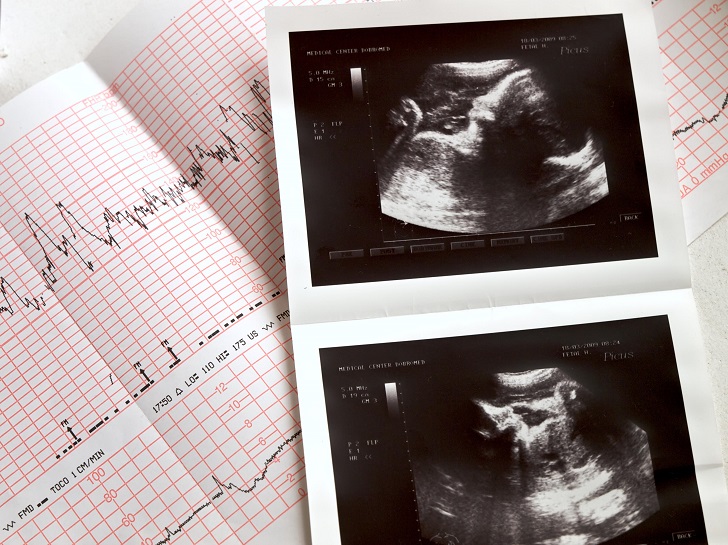

حقیقت: جامعه ی پزشکی مدت ها قبل این شیوه را رد کرده است. در سال ۲۰۰۶، تحقیقی نشان داد هیچ ارتباطی میان جنسیت جنین با میزان ضربان قلبش در سه ماهه ی نخست بارداری وجود ندارد. قلب بچه ها به طور کلی طی ۲۸ تا ۳۰ هفته ی اول بارداری سریع تر می زند.